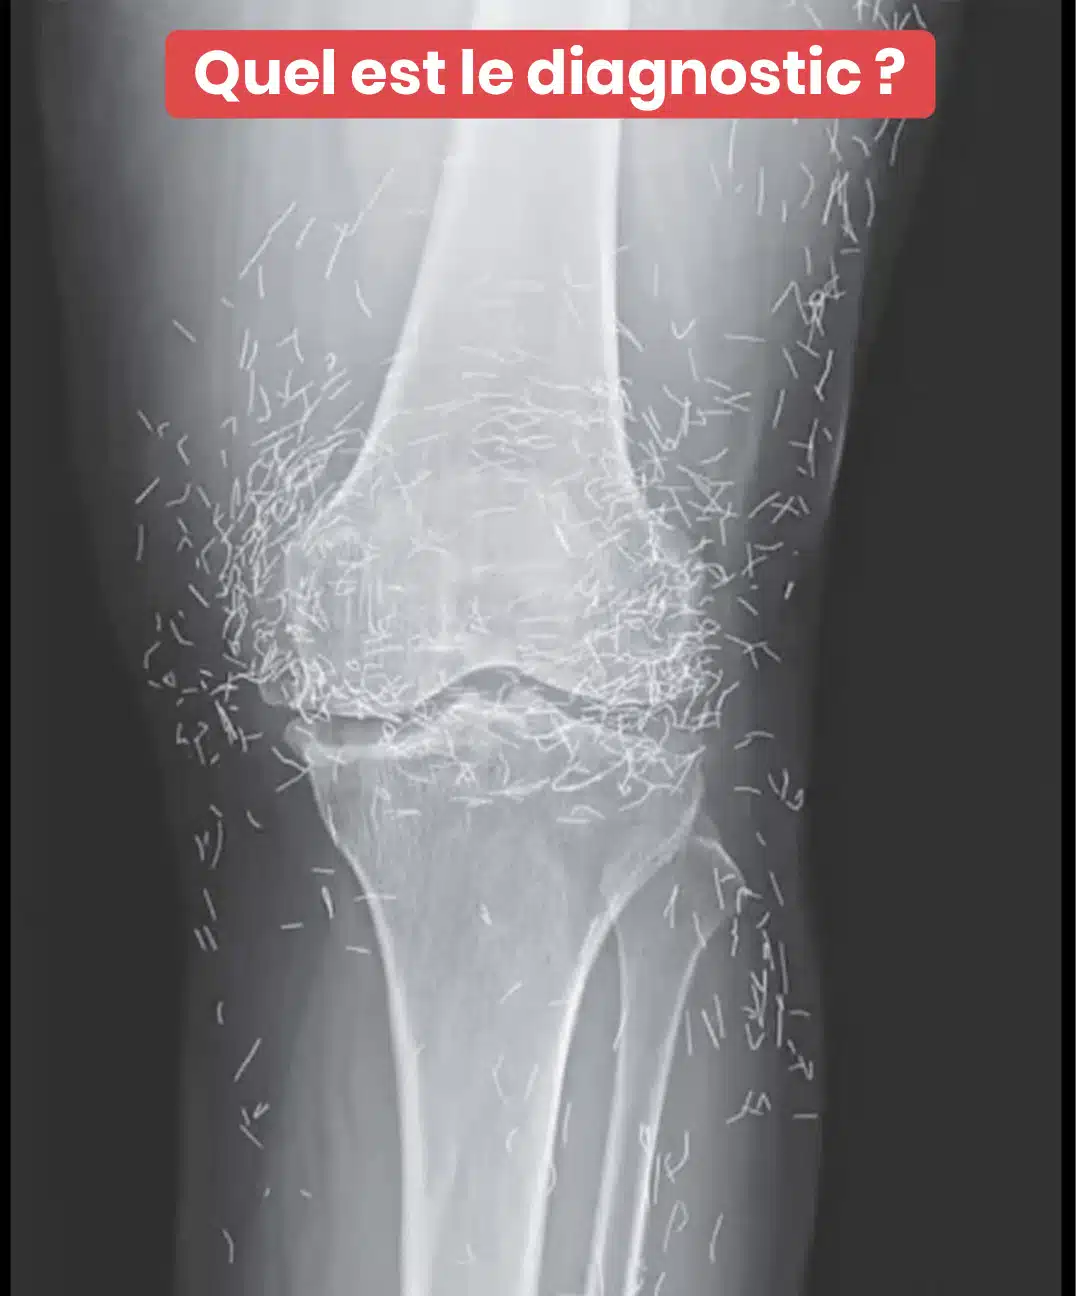

Une simple radio des genoux a révélé une surprenante découverte chez une sexagénaire : des centaines de micro-aiguilles en or disséminées dans ses articulations. Cette révélation médicale met en lumière une pratique thérapeutique méconnue en Occident mais répandue en Asie. Plongée dans une aventure où médecine moderne et traditions ancestrales se rencontrent de façon spectaculaire.

Au cours de ses traitements, cette dame a bénéficié de l’insertion de fines aiguilles en or autour de ses articulations sensibles. Différemment de l’acupuncture traditionnelle où les aiguilles sont retirées après chaque session, ces micro-implants ont été délibérément laissés dans ses tissus. L’ambition ? Prolonger durablement les effets thérapeutiques de la stimulation acupuncturale.

Cette approche, parfois nommée « acupuncture permanente », continue d’être utilisée dans certaines régions d’Asie, particulièrement pour apaiser les douleurs persistantes. On insère alors de minuscules fragments d’or ou d’acier chirurgical, parfaitement stériles, qui demeurent en place… potentiellement pendant plusieurs années, voire indéfiniment.

C’est à l’occasion d’un examen d’imagerie médicale routinier que les praticiens ont observé, stupéfaits, la présence de centaines de petites aiguilles scintillantes réparties autour de ses articulations du genou. Une véritable énigme clinique qui a provoqué autant de fascination que de circonspection. Car si l’or présente une excellente tolérance biologique, la persistance d’éléments étrangers dans l’organisme n’est jamais dénuée de conséquences.

Selon des experts en radiologie, ces implants métalliques peuvent occulter certaines structures anatomiques sur les clichés radiologiques, compliquant ainsi le dépistage d’autres affections. Plus préoccupant encore : ils représentent une contre-indication sérieuse à l’IRM, puisque le risque de migration des aiguilles sous l’effet des champs magnétiques existe bel et bien, avec un potentiel de lésions tissulaires.